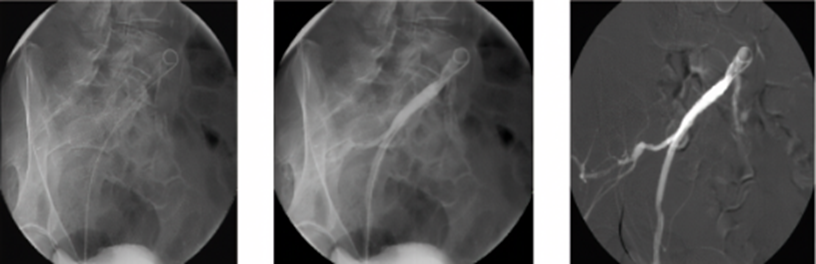

目前,超声、血管造影 (CTA、MRA、DSA)、PET、PET/CT 及 PET/MR 等方法均被应用于动脉硬化和易损斑块特征的分析。

2、CT血管成像(CTA) CTA 可多方位成像,有较好的空间分辨力和扫描速度快等优势,适用于观察不易发现的早期血管病变。因辐射和造影剂的影响,CTA禁用于严重肝肾功能异常及有过敏史者。双能CT图像的质量更高,其应用前景有待进一步实践。

3、磁共振血管成像(MRA) 磁共振成像(MRI)通过无创成像方法,可动态观察血管的狭窄程度、斑块的体积大小及演变过程;对斑块成分及表面形态,包括纤维帽破裂和溃疡,加以分析,并对加速粥样病变进程的危险因子加以测评

5、数字减影血管造影(DSA DSA被认为是诊断颈动脉疾病的金标准和评价颈动脉狭窄及闭塞的最佳方法。但对血管壁 的 病 变 显 示欠佳,对斑块大小及形态、成分及易损性很难评估。同时该检查有创,容易诱发斑块脱落、血管壁损伤、夹层动脉瘤、动脉瘤、穿刺部位血肿等医源性损伤,在实行有创介入治疗时可考虑,不作为一线检查手段。